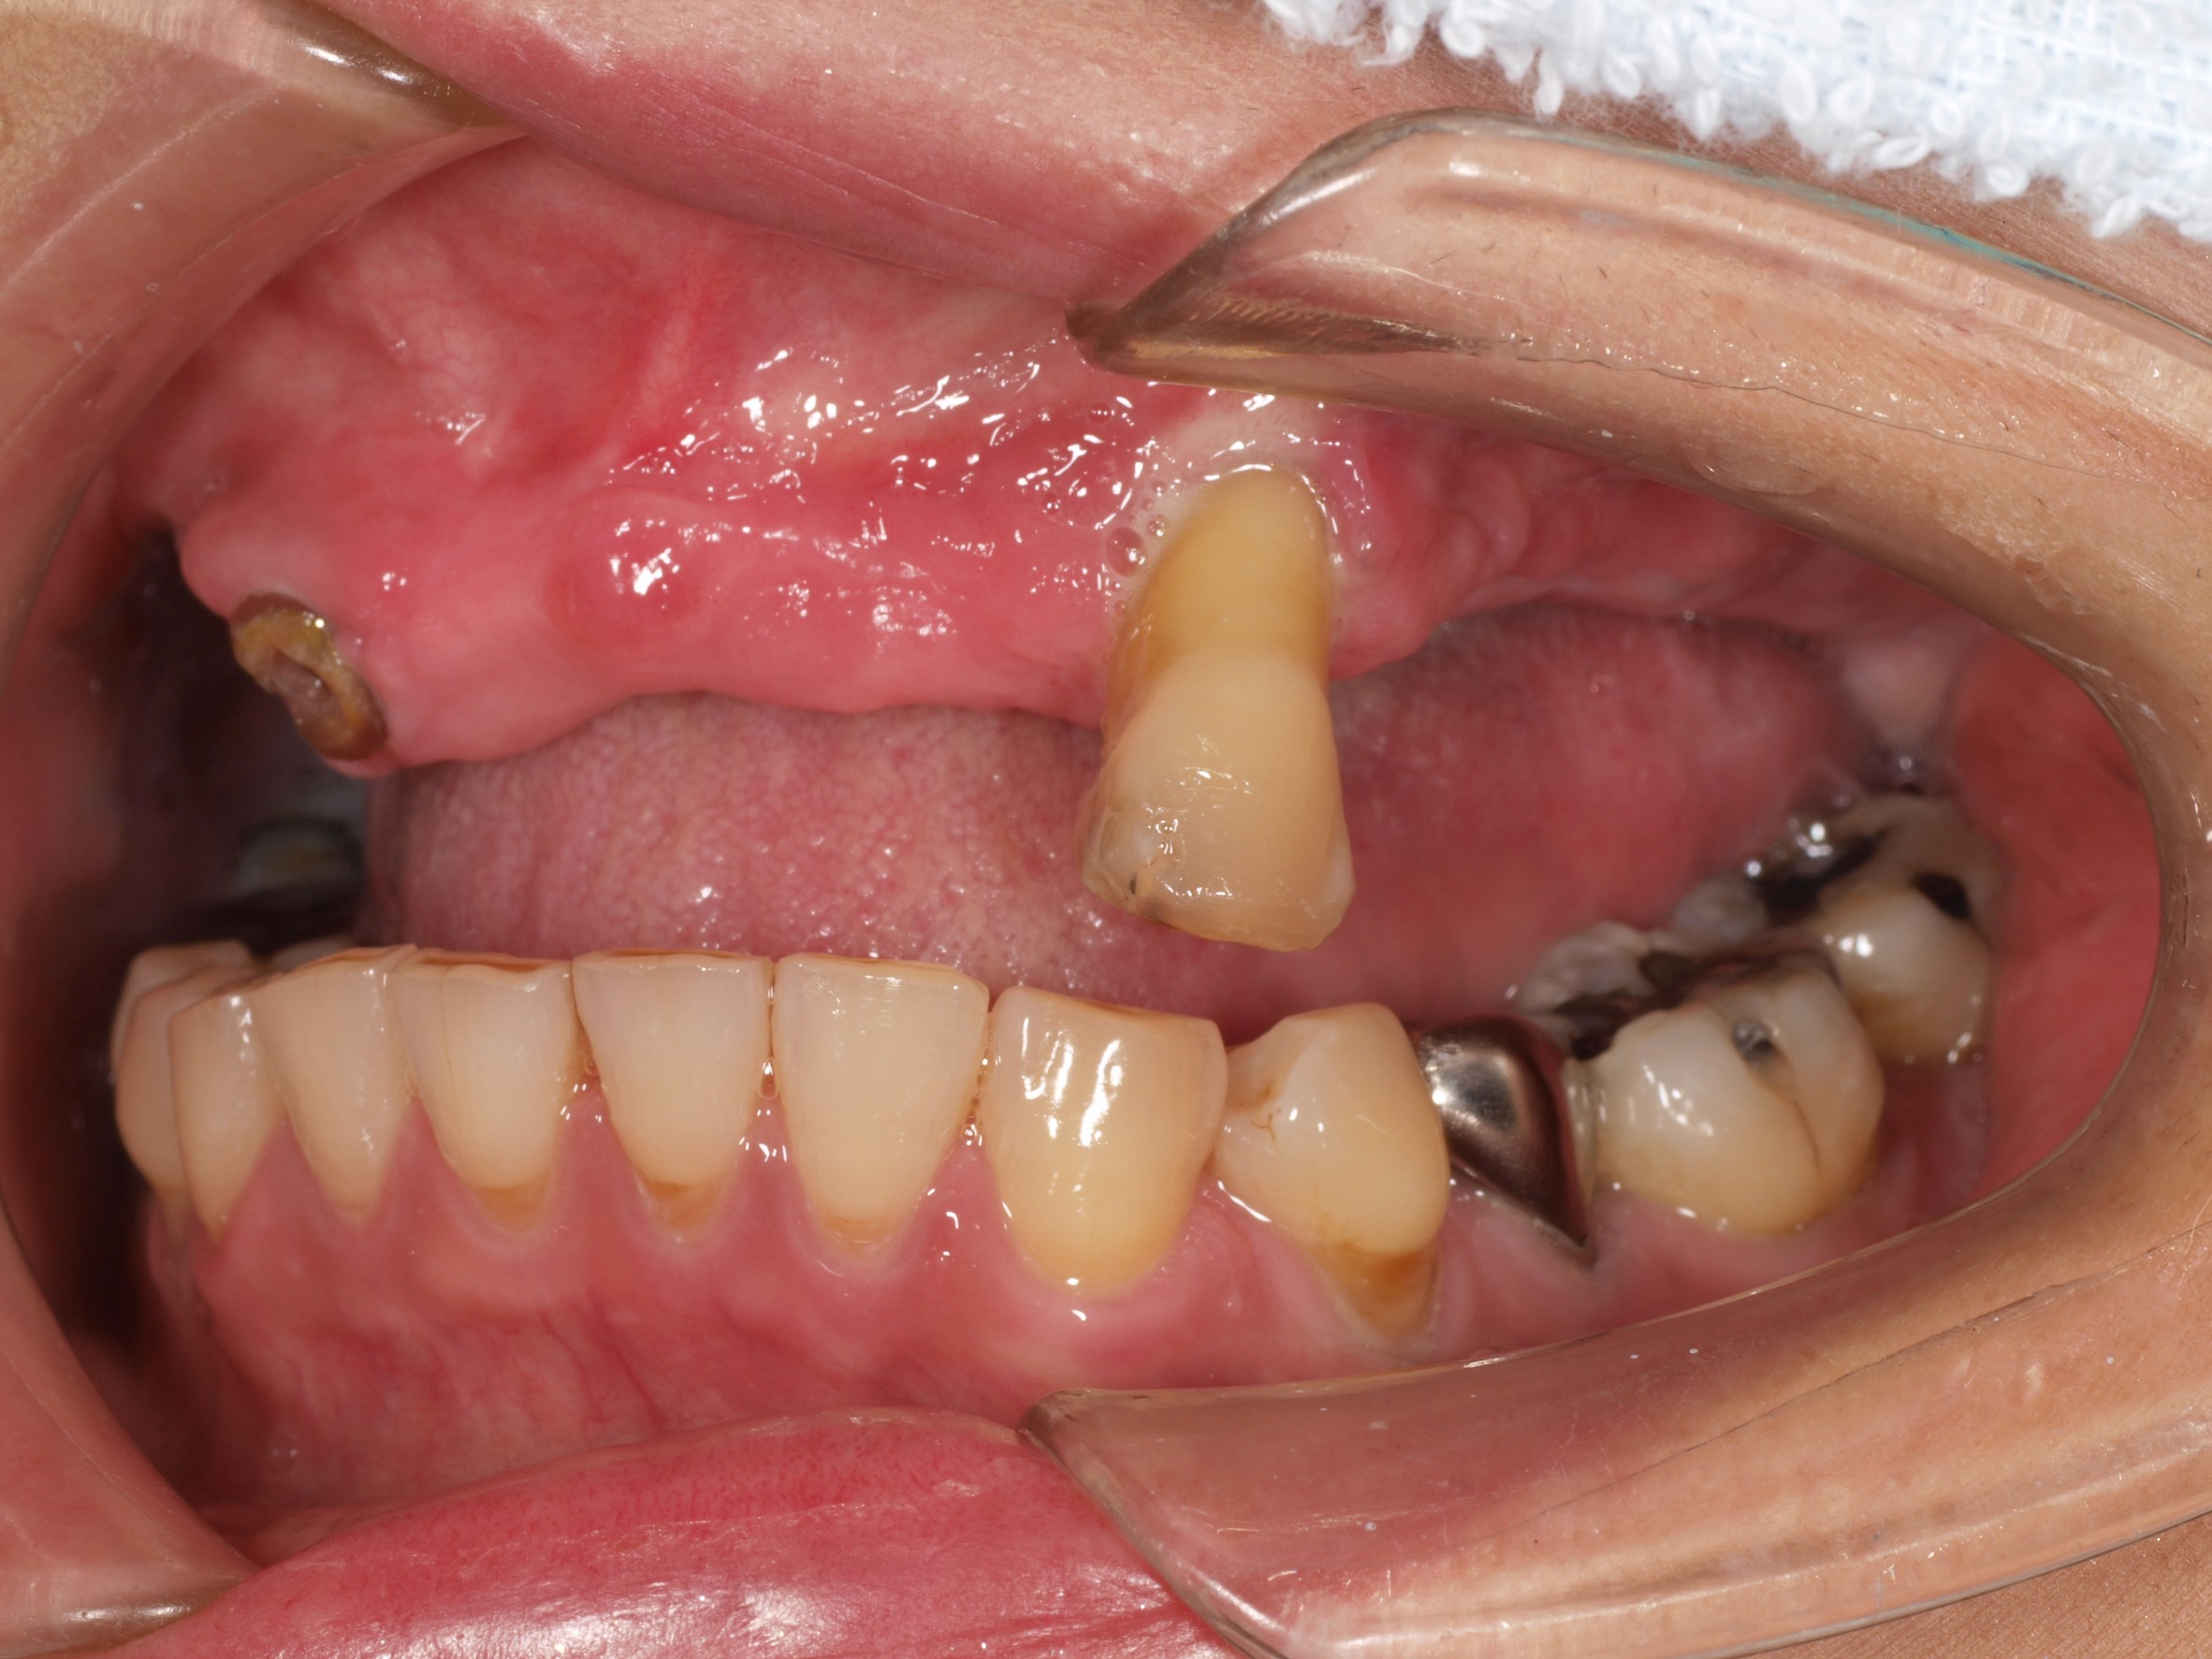

症例紹介

- 主訴

- 入れ歯が合わない。食べにくい。人生を豊かにしたい。

- 処置内容

- 上顎4本で12歯(オールオン4)、下顎4本5歯。

上下抜歯即時埋入、即時荷重(手術当日にインプラントの上に仮歯装着)

- 治療費用

- 上顎:約290万(税込)、下顎:約210万円(税込)

- 治療期間・通院回数

- 上顎:9か月/9回

下顎:6か月/7回

- リスク

- 術後の腫れ、痛み(ピークは3日後、1週間で軽減)

上部構造物、仮歯の破折、人工歯根脱落リスクがあります